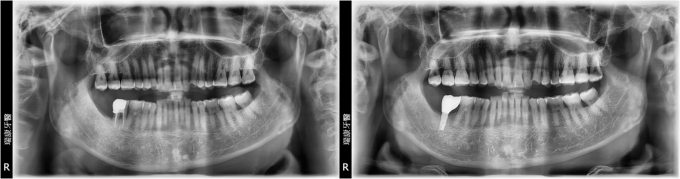

下顎多顆缺牙重建

病患呂小姐,65年次,家庭主婦

主訴 : 右下牙橋搖晃嚴重,想重建

治療計劃: 拔除嚴重牙周病之牙齒,等待三個月癒合期, 安排精密3D電腦斷層評估後,進行人工植牙, 三個月後接出假牙基座印模製作正式假牙!

實例照片僅為資訊介紹及分享,效果可能因個人體質及保養方式不同而有所差異。